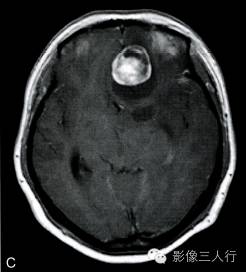

A.T1横断面;B.T2WI横断面;C、D、E~增强横断面、矢状面、冠状面;F.HE×100

图A、B:T1WI、T2WI横断面,图C~E为增强横断、矢状位及冠状位。左额底部见一囊性肿物,囊内见一直径约28mm类圆形肿块,边界清,T2WI呈不均匀高信号为主,内混杂条片状稍低信号,T1WI呈稍低信号,周边见环形稍高信号;增强后病灶大部呈明显强化,内可见不规则无强化区;灶周见液性信号影环绕,并可见大片状不规则水肿,累及左额颞叶、左基底节前部及左侧胼胝体膝部;邻近脑组织受压明显,左侧脑室、右侧脑室前角、3脑室及鞍上池受压变形,前部中线结构右移。